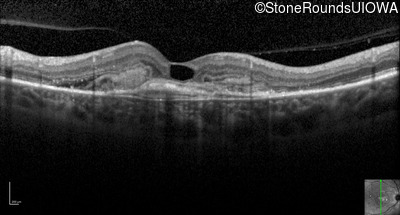

Optical Coherence Tomography - Right - 20/250

Exemplar / OCT Stack

Optical Coherence Tomography - Left - 20/20 -1